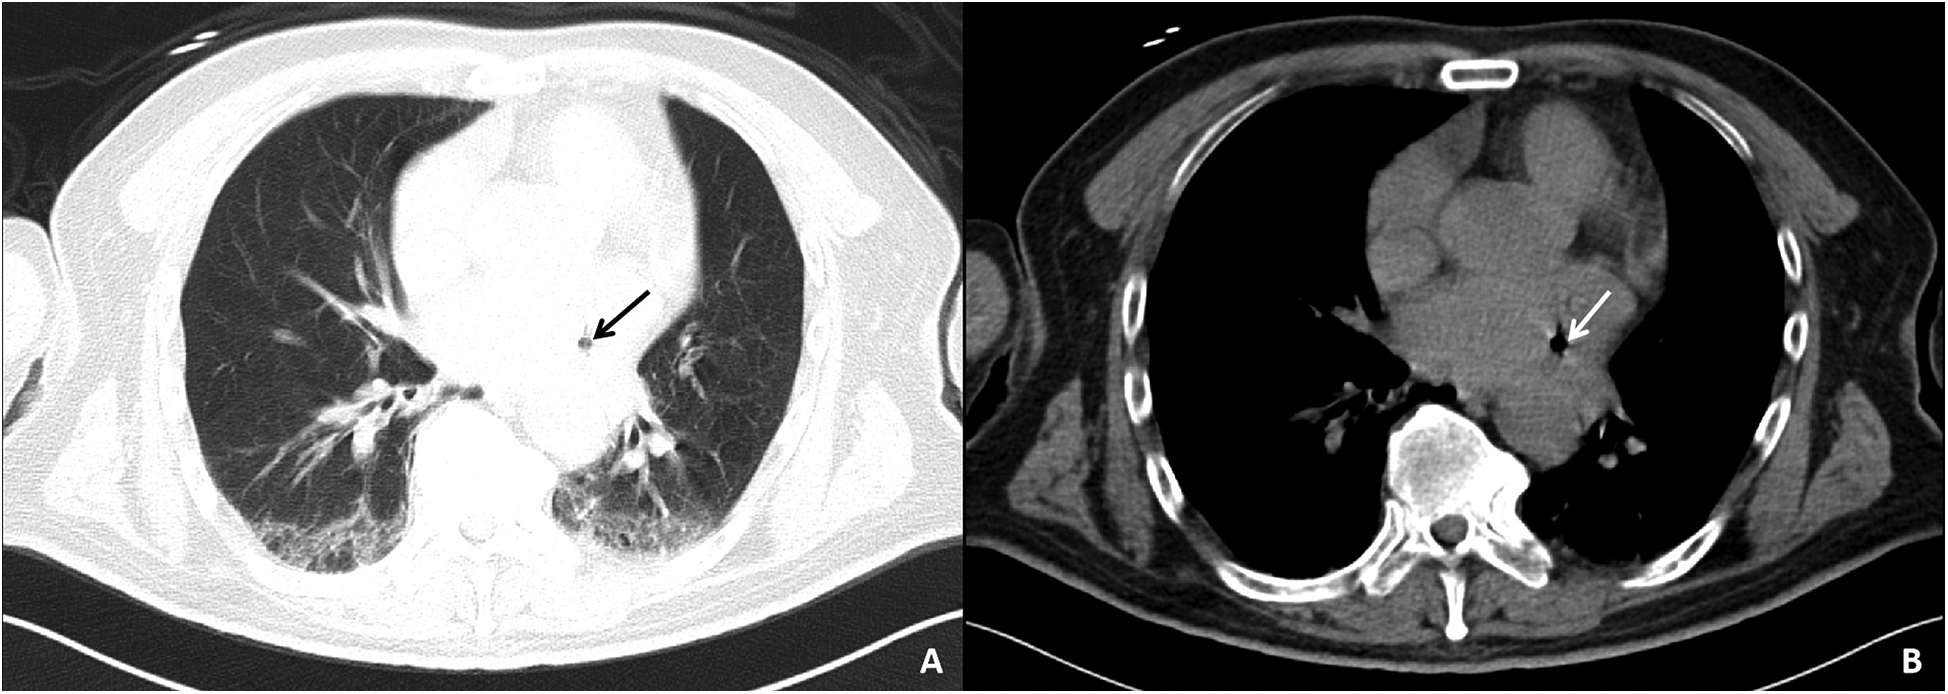

Auxiliary examinations included cerebral artery computed tomography angiography (CTA), which revealed cerebral atherosclerosis with mild local luminal stenosis. CT scans of the head and chest revealed a slightly hypoattenuating area in the right frontoparietal junction (Figure 1) and a radiolucent area in the left atrial region suggesting possible air accumulation (Figure 2). Specifically, the cranial CT images upon admission showed slightly lower density areas with unclear boundaries, primarily located in the white matter region of the right parietal lobe, indicative of an acute ischemic event rather than chronic changes. The presence of these hypodense areas, combined with the patient's clinical presentation and elevated troponin levels, suggested an acute ischemic stroke. These findings warranted further investigation. Electrocardiogram (ECG) findings indicated atrial flutter with rapid ventricular response, ST-segment elevation in the inferior leads with abnormal Q waves, and incomplete right bundle branch block (Figure 3A). The patient had a history of atrial fibrillation and had undergone RFA one month prior at another hospital. The provisional diagnoses included cerebral infarction, shock, coma, and heart failure. The patient's history included RFA for atrial fibrillation. As the patient was within the therapeutic window for stroke, treatment with 1 million IU of urokinase for thrombolysis was initiated with consent. Urokinase, a fibrinolytic agent effective in dissolving clots and restoring blood flow, was chosen for its balanced safety and efficacy, especially crucial for rapid reperfusion. Compared to alteplase (tPA), urokinase may reduce the risk of systemic bleeding complications in certain patients. Symptomatic and supportive measures, including fluid resuscitation and vasopressor support, were provided to improve cerebral circulation and for early secondary prevention of stroke. Continuous monitoring of cardiac and hemodynamic parameters was also conducted.

Figure 2

Chest CT images of the patient upon admission. The pulmonary window (A) and mediastinal window (B) both show a lucency in the area of the left atrium, suggesting a small amount of air within the left atrium.